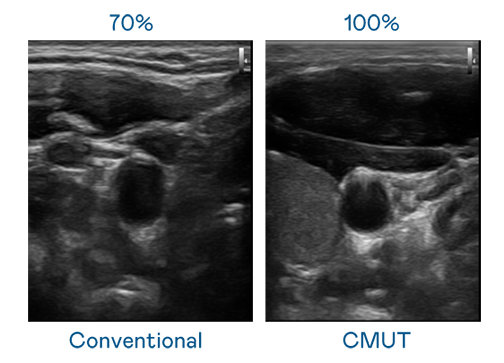

CMUT 技术是一种用电容式微机电元件来产生超音波讯号的技术。与传统 PZT 压电式技术相比,CMUT 频宽增加 30%,更宽频的超音波讯号让影像解析度大幅提升,是实现高影像品质医疗超音波扫描、促进精准医疗发展的关键技术。

大频宽带来超清晰影像

超音波影像的解析度高低,首先取决于探头能发出的讯号频宽。门徒娱乐 CMUT 可提供高清晰的超音波讯号,提供高频宽、高灵敏度、影像纹理细节更高的超音波影像,协助医护人员缩短影像判读时间及利用精准的医疗影像进行诊断。